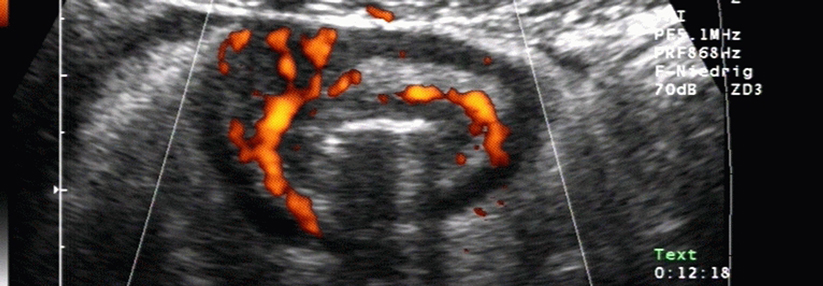

Der monoklonale IgG1-Antikörper Risankizumab könnte dabei helfen, Morbus Crohn in den Griff zu bekommen: Der Wirkstoff führte in aktuellen Studien zu einer signifikanten klinischen Remission und ermöglichte eine langfristige Stabilisierung.

Trotz zahlreicher medikamentöser Optionen gelingt es in vielen Fällen nicht, einen Morbus Crohn in den Griff zu bekommen. Eine neuartige Klasse von Biologika verspricht Hoffnung: Der monoklonale IgG1-Antikörper Risankizumab führte in zwei aktuellen Phase-3-Studien zu einer signifikanten klinischen Remission. Zeitgleich wurde eine weitere Phase-3-Studie veröffentlicht, in der durch eine subkutane Erhaltungstherapie ein erheblicher Teil der Fälle langfristig stabilisiert werden konnte. Risankizumab bindet selektiv an die p19-Untereinheit von IL-23, berichten Prof. Dr. ­Marc ­Ferrante von der Universität Löwen und Kollegen. Das Zytokin spielt eine zentrale Rolle bei der Pathogenese des Morbus…